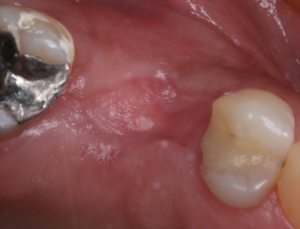

Vista oclusal do alvéolo logo após a remoção da membrana Cytoplast.

Vista oclusal do alvéolo após quatro meses da exodontia e ROG.